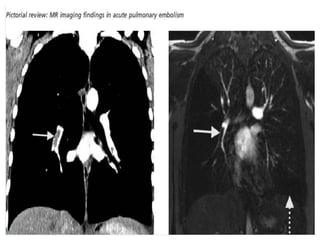

(a) CT angiography shows thromboembolic material in both lower lobe pulmonary arteries

(arrows). (b) High spatial resolution MR angiography demonstrates the same findings

(arrows).

(a) CT angiographyshows thromboembolic material in both lower lobe pulmonary arteries (arrows). (b) High spatial resolution MR angiography demonstrates the same findings (arrows).